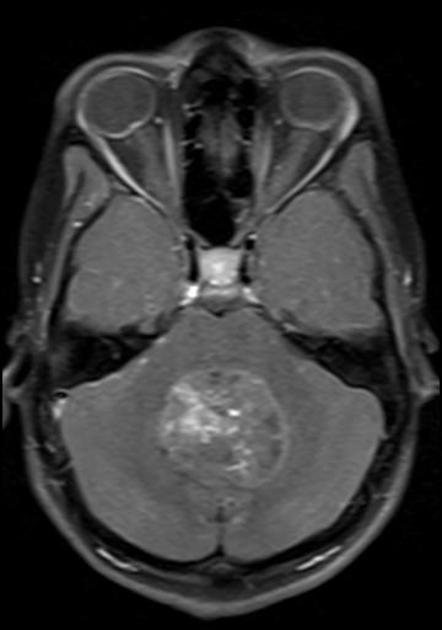

Axial T2Sagital FLAIR

Axial T1Axial T1 GadAxial T1 Gad/fat sat

For a detailed discussion of ependymoma imaging see Radiopedia for an excellent discussion on ependymoma imaging by Weerikoddy and Galliard.

MRI Brain

Careful examination of the entire neuraxis is required to assess for the presence of CSF seeding.